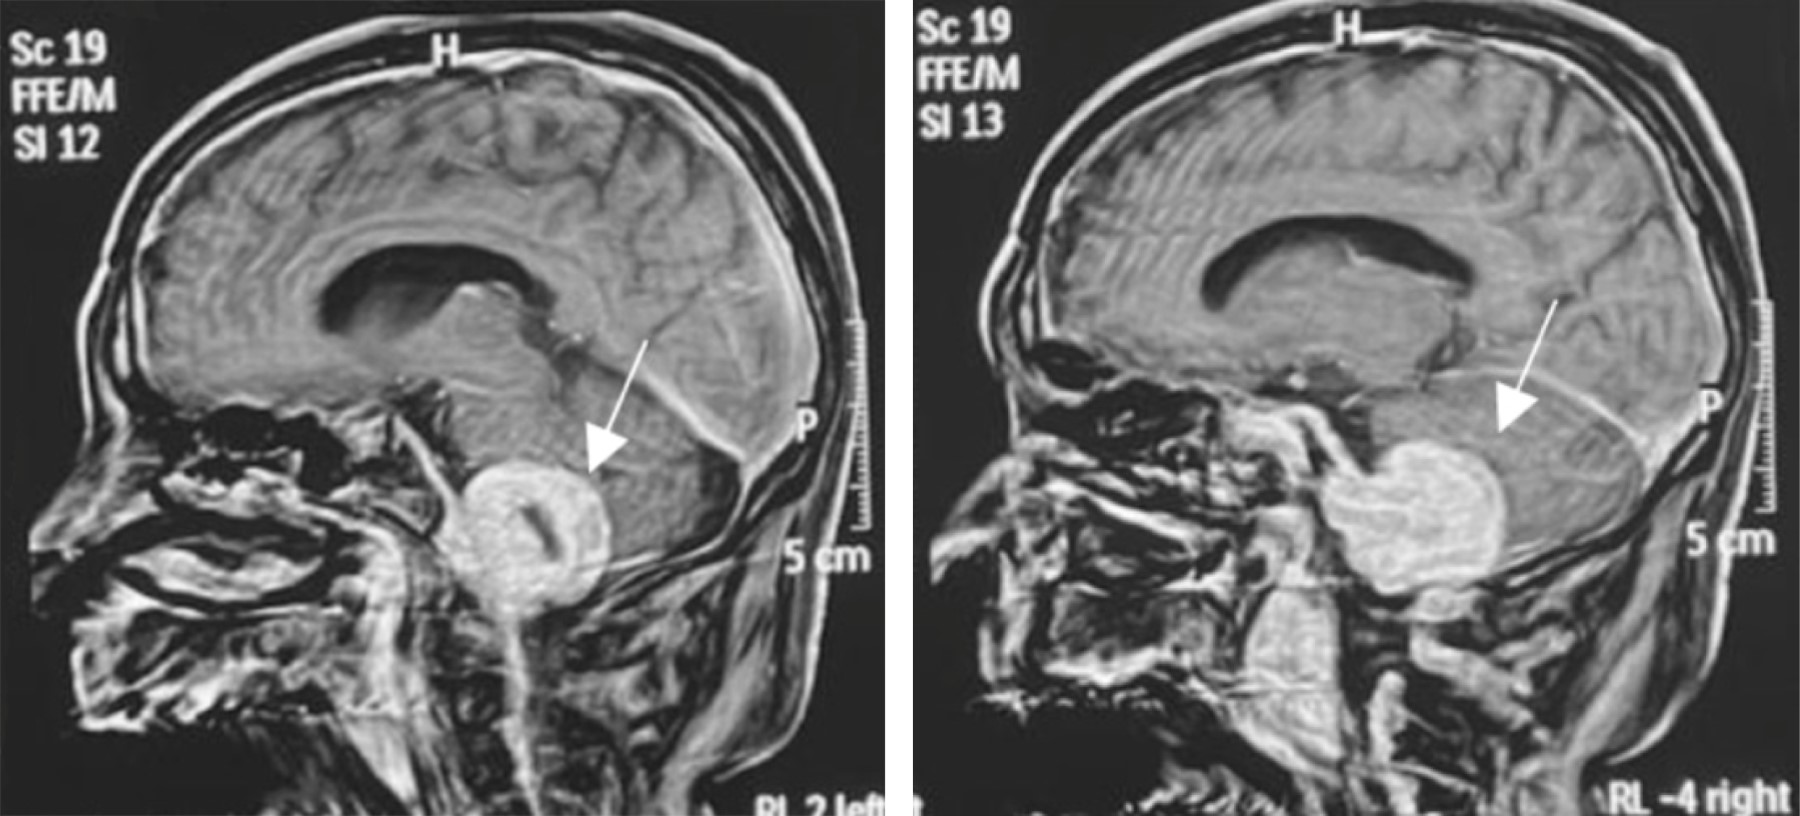

Figure 2